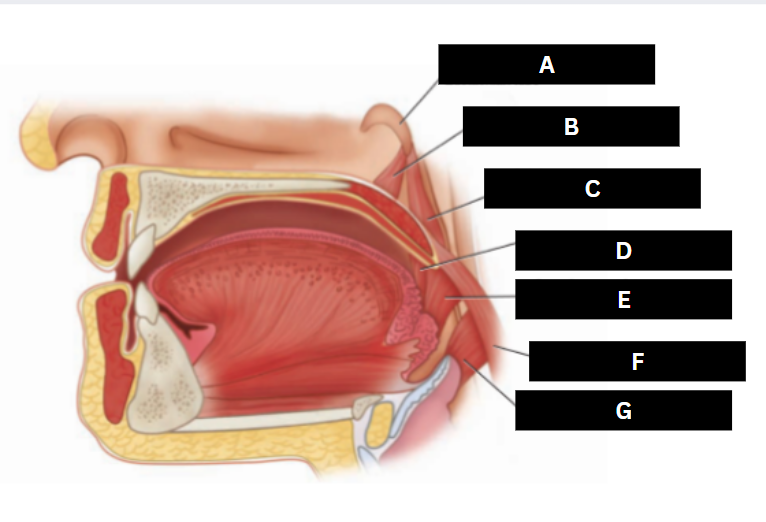

Eustachian tube

A

Levator veli palatini

B

Salpingopharyngeus

C

Palatoglossus

D

Superior pharyngeal constrictor

E

Palatopharyngeus

F

Middle pharyngeal constrictor

G